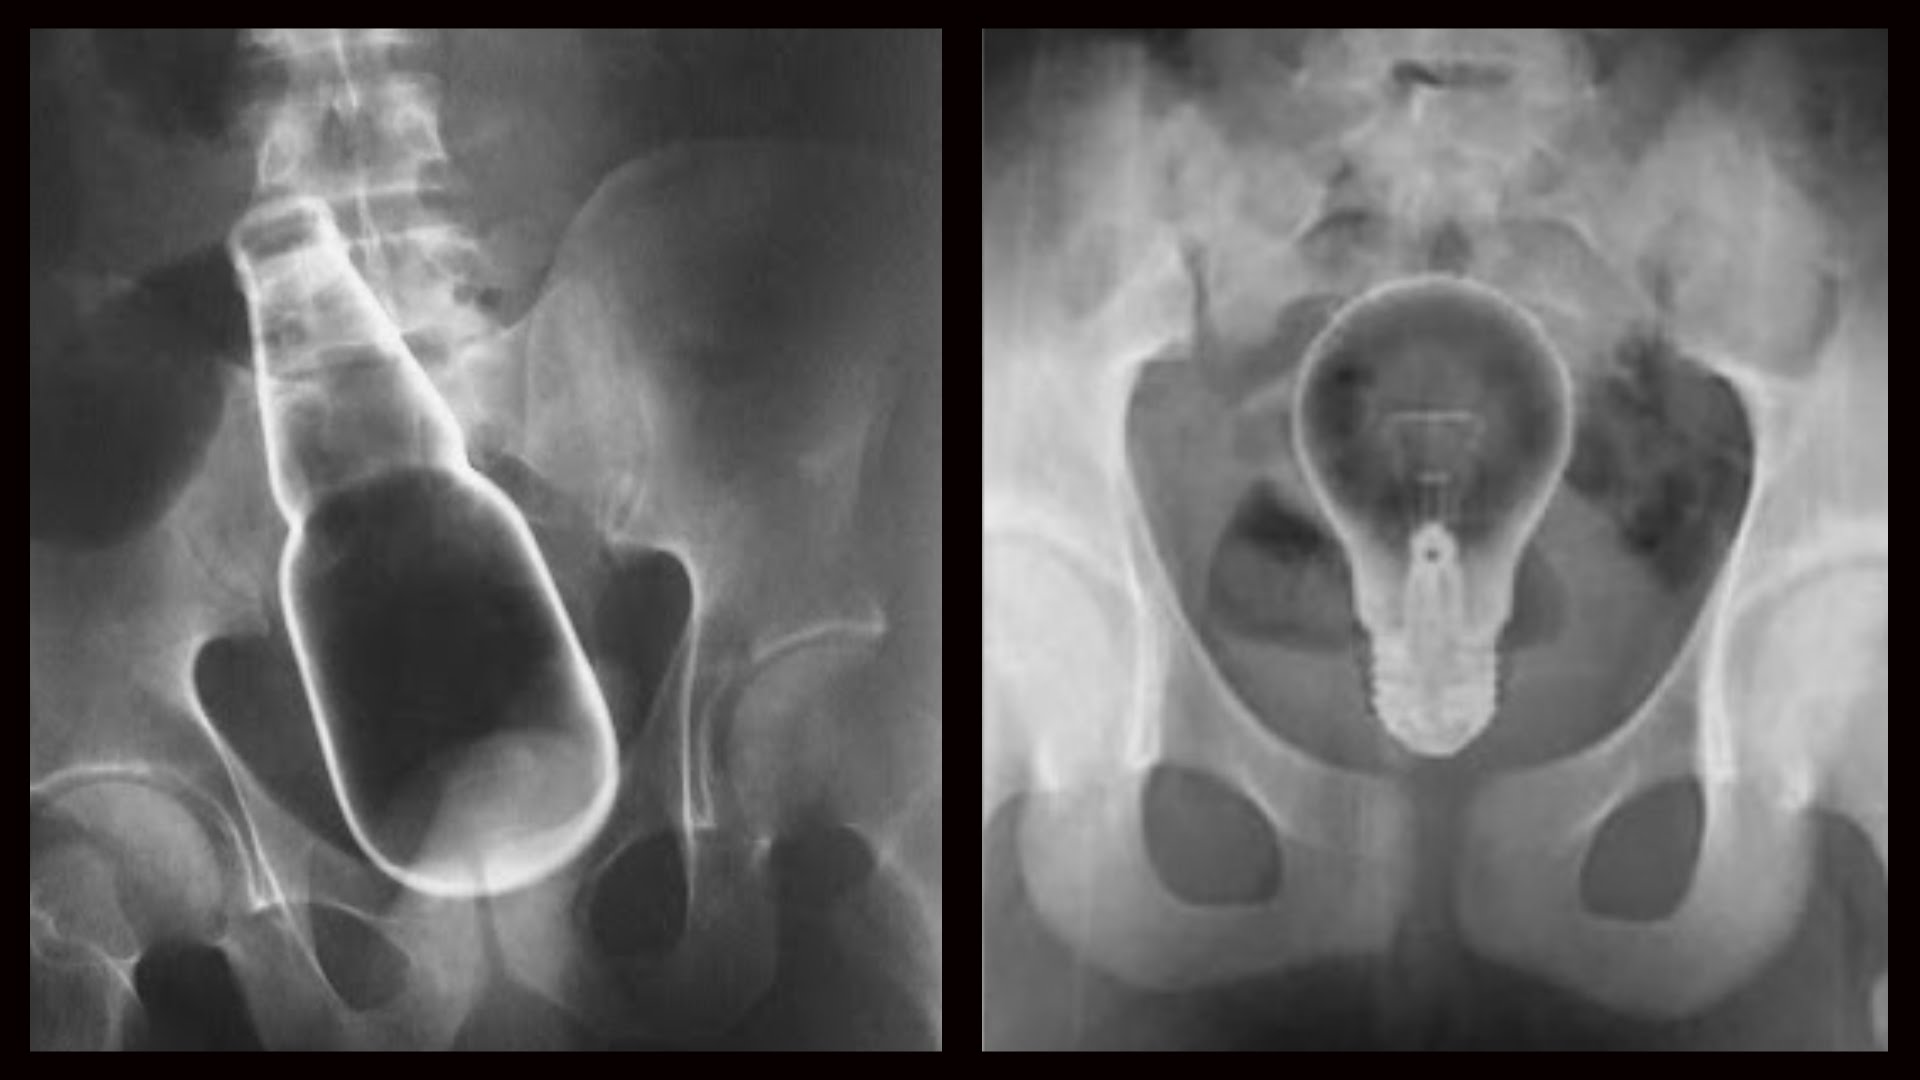

Strange object 01.jpg Strange object 02.jpg Strange object 03.jpg Strange object 07.jpg Strange object 10.jpg Подборка странных предметов, обнаруженных в человеческом теле. Пожалуй, элемент смешного присутствует ))) Хотя "носителям" вряд ли до смеха. )) Впрочем, кто им виноват?